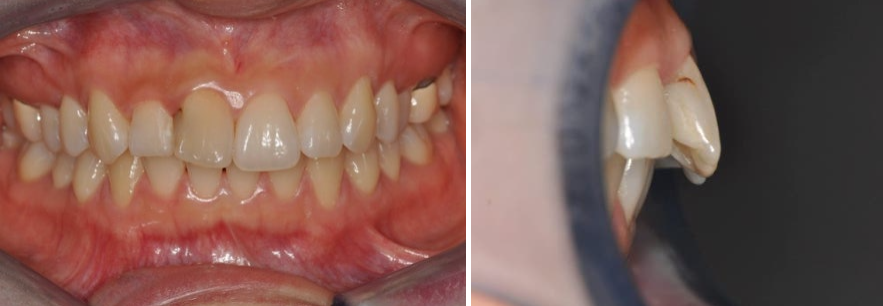

케이스 2. 수직·수평 문제는 부분교정만으로 한계가 있는 경우

이 케이스에서도

위 앞니와 아래 치아 사이의 수평적 거리(앞뒤 간격) 는 먼 편이었지만,

치아 배열 자체를 방해하는 치아는 크게 없었습니다.

다만, 앞선 케이스와 마찬가지로 앞니가 깊게 물리는 상태(Deepbite) 였습니다.

이때 중요한 점은,

깊게 물리거나, 아주 얕게 물리는 등 수직적인 문제,위·아래 앞니 사이의 간격이 너무 멀거나 반대로 거꾸로 물리는 수평적인 문제는앞니 부분교정만으로 해결하는 데 분명한 한계가 있다는 것입니다.

이 환자분도 윗니 부분교정을 통해

배열은 훨씬 가지런해졌고,

정면에서 보이는 심미성은 개선되었습니다.

하지만 치료 후에도

수직적인 Deepbite 문제와

수평적인 거리 문제는 크게 개선되지 않았습니다.

결국, 이 케이스 또한

“부분교정으로 배열은 예뻐졌지만,장기적인 안정성과 교합 측면에서 아쉬움이 남는 경우”

라고 할 수 있습니다.